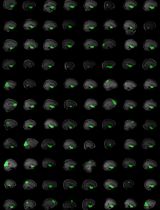

Normative mapping is a framework used to map population-level features of health-related variables. It is widely used in neuroscience research, but the literature lacks established protocols in modalities that do not support healthy control measurements, such as intracranial electroencephalograms (icEEG). An icEEG normative map would allow researchers to learn about population-level brain activity and enable the comparison of individual data against these norms to identify abnormalities. Currently, no standardised guide exists for transforming clinical data into a normative, regional icEEG map. Papers often cite different software and numerous articles to summarise the lengthy method, making it laborious for other researchers to understand or apply the process. Our protocol seeks to fill this gap by providing a dataflow guide and key decision points that summarise existing methods. This protocol was heavily used in published works from our own lab (twelve peer-reviewed journal publications). Briefly, we take as input the icEEG recordings and neuroimaging data from people with epilepsy who are undergoing evaluation for resective surgery. As final outputs, we obtain a normative icEEG map, comprising signal properties localised to brain regions. Optionally, we can also process new subjects through the same pipeline and obtain their z-scores (or centiles) in each brain region for abnormality detection and localisation. To date, a single, cohesive dataflow pipeline for generating normative icEEG maps, along with abnormality mapping, has not been created. We envisage that this dataflow guide will not only increase understanding and application of normative mapping methods but will also improve the consistency and quality of studies in the field.